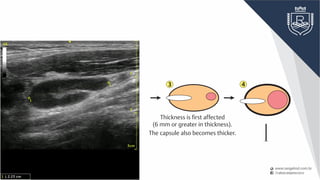

No changes in the size or form

Thickness is first affected

(6 mm or greater in thickness).

The capsule also becomes thicker.